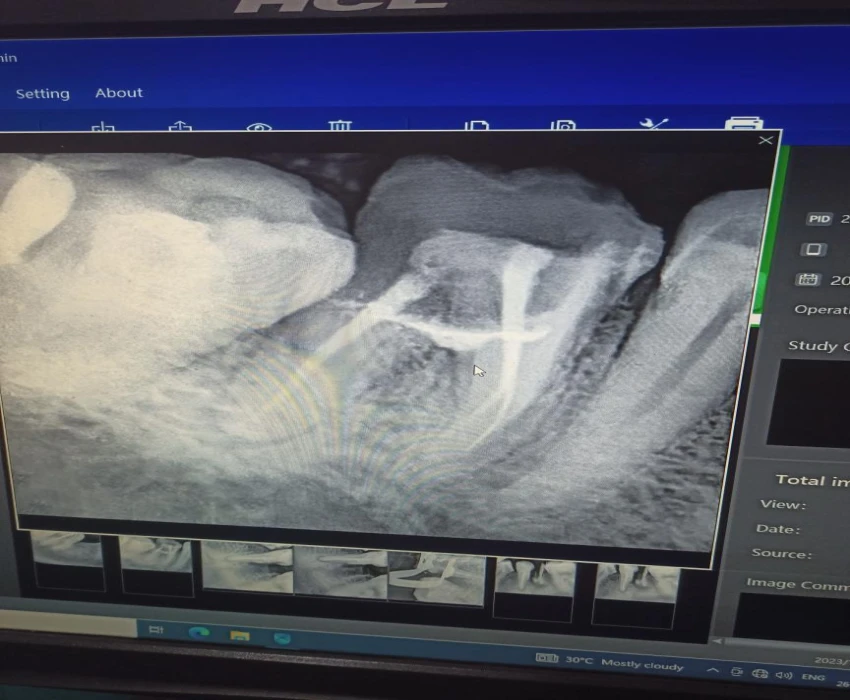

Perforation was detected clinically and radiographically after the removal of caries from the grossly carious tooth.

Canals were located and the working lengths were determined. Canals prepared with crown down technique and obturated using Gutta percha points using lateral condensation technique .

The perforation is sealed with mineral trioxide aggregate-sterile saline paste mixed according to the manufacturer's direction.A cotton pellet was then placed in the pulp chamber to produce a humid ambient for the MTA with the aim of achieving its solidification, and the tooth was temporary filled with Cavit temporary restoration material.

The patient returned to the hospital three days later with no symptoms or signs.

Temporary sealing materials and the wet cotton pellet were removed and the hardness of the MTA was gently tested with an operative explorer. The remaining cavity was filled with GIC . And the patient was kept on follow up for 15 days.